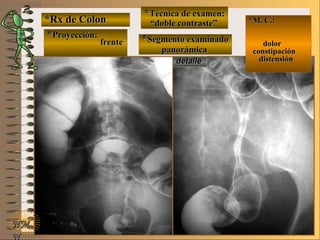

*Rx de Estómago*Rx de Estómago

**Proyección:Proyección:

**Técnica de examen:Técnica de examen:

A-A-

B-B-

C-C-